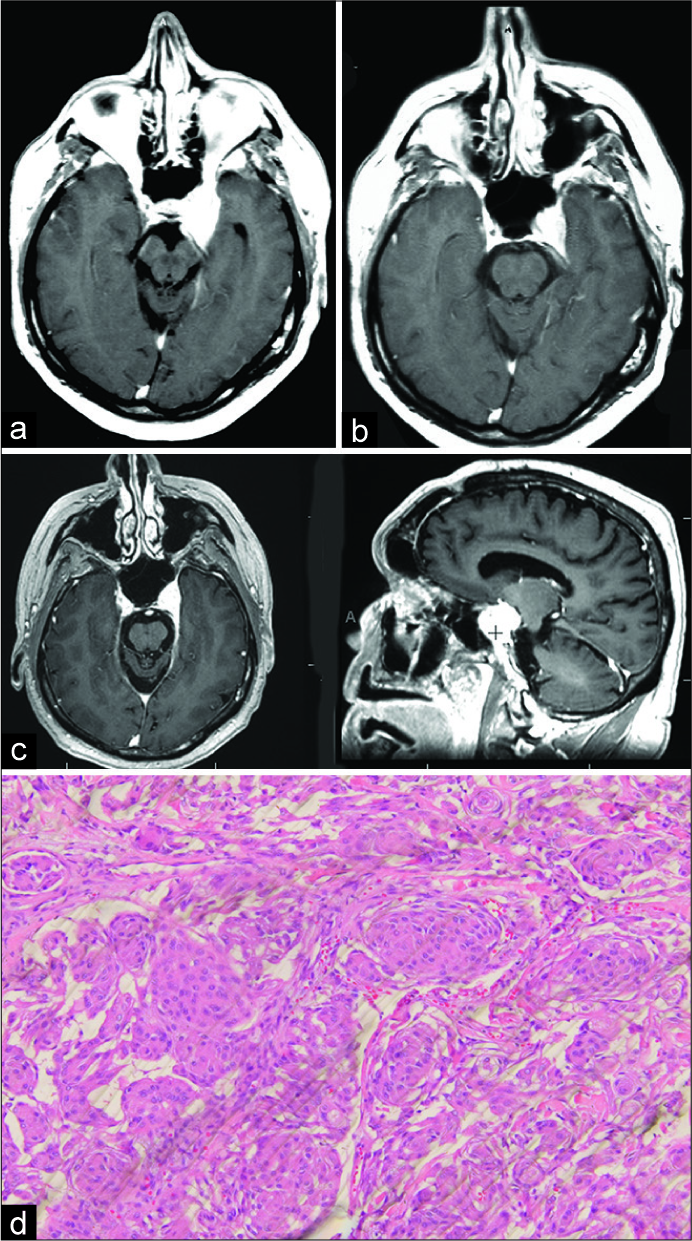

1例38岁女性,因轻度眼球突出,3神经麻痹复视,左眼视力下降,于1981年入院复查[图3a]。她于1982年被诊断为蝶骨翼脑膜瘤并进行了手术。手术中,切除了一小部分肿瘤。然而,根治性切除被避免。她没有接受任何放射治疗。在随访中,除3神经麻痹外,尽管肿瘤生长缓慢,但未出现其他并发症[图3b-d]。多年来,她一直保持活跃和健康,直到2018年因卵巢癌去世,享年88岁。

图3

1994年,一名48岁男子因左VIth神经麻痹引起复视。扫描显示CSM(扫描不再可用)。在手术中,肿瘤部分切除没有进入海绵窦深,然后是常规放疗。术后复视恢复,扫描显示肿瘤残留[图4a-c]。组织学见图4d。患者可以重返工作岗位,2017年的扫描显示肿瘤没有明显增大。写这篇论文的时候,病人还活着。

图4